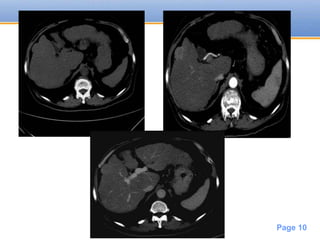

CT

• Focal HCC

large usually hypodense mass

may have necrosis / fat / calcification

• Multifocal HCC

multiple masses of variable attenuation may also

have central hypodense necrotic portions

• Diffuse HCC

may be difficult to distinguish from associated

cirrhosis

Enhancement pattern

• Transient early arterial enhancement and

then washes out

• #11 HCC Cirrhotic liver with a single nodule in the right lobe showing marked arterial phase enhancement and early wash off in the portovenous phase are diagnostic features of a HCC.

• #26 focal, multiple or diffusely infiltrating A capsule is usually best seen in the delayed phase as a relative hyperdense structure.

• #27 the larger the lesion the more heterogeneous the enhancement becoming indistinct or hypodense compared to the rest of the liver at the portal phase Area of necrosis -> low density non enhancing Tumor thrombosis of portal vein will also shows enhancement